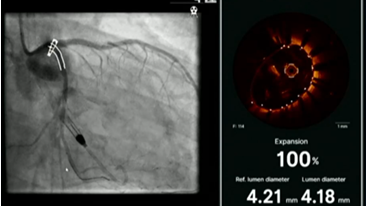

来自挪威的Anja Oksnes教授指出,应用一根IVL导管可对多个分支钙化病变处进行治疗。由于IVL C2导管最多有80次脉冲(8个周期),因此可以根据钙化病变程度,合理分配IVL的脉冲次数,对不同区域的钙化组织进行修饰破碎,从而实现一根导管对多处钙化病变进行治疗的目的,且IVL可以在冠状动脉分叉处进行治疗(如图12)在分叉病变可以保留伴行导丝,保护边支血管。

图片

图12